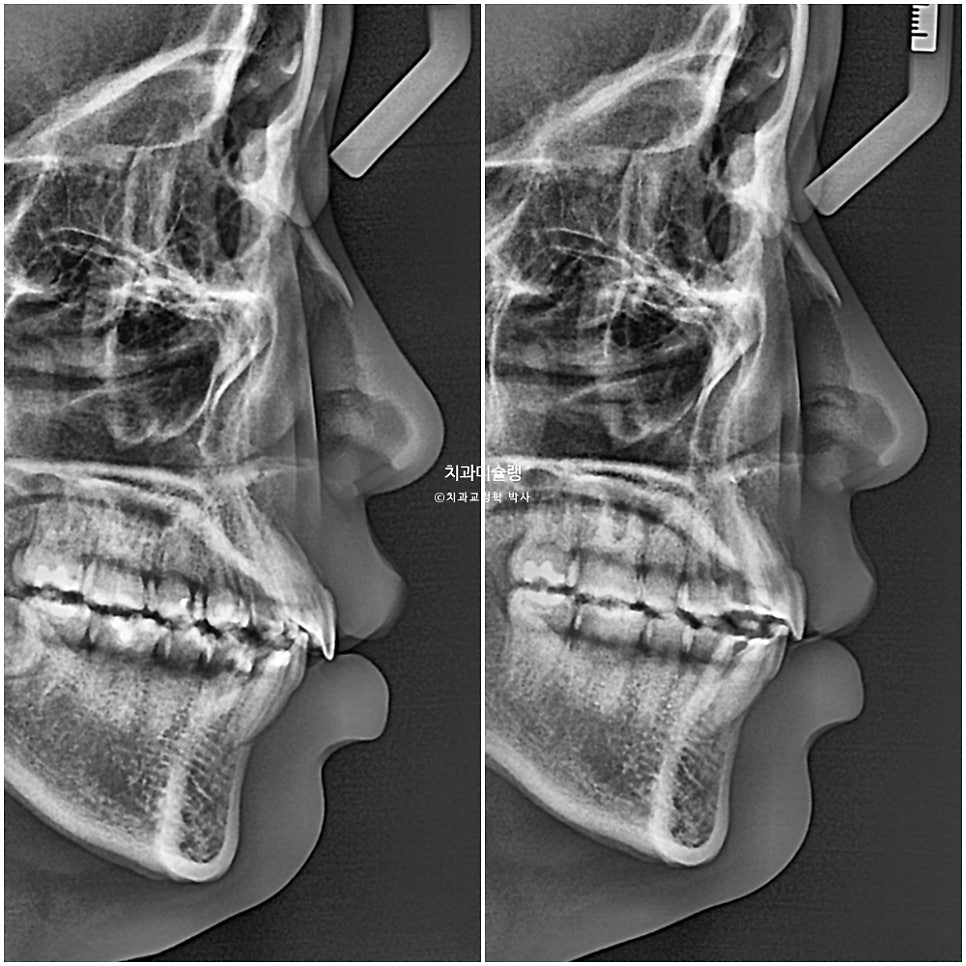

본원에 과거 4월 교정 전 엑스레이 자료가 있어 현재 11월 상태와 객관적으로 중첩을 해보았습니다.

까만선이 24년 4월 초진, 빨간선이 24년 11월 입니다. 2급 고무줄을 끼면서 위 앞니와 어금니를 포함한 전체치열이 뒤로 소량 들어가고 아래 전체치열은 앞으로 소량 나온것이 확인됩니다.

과개교합이라도 먼저 해결을 한 후 2급 고무줄을 꼈다면 모를까, 과개교합 개선이 안된 상태에서 이러한 치아이동은 앞니에 더 심한 교합간섭을 만들고 다물때 아래턱이 뒤로 밀리는 증상이 생길 수 밖에 없죠. 아래턱이 뒤로 밀리면 관절공간을 압박하여 턱관절 통증이 생길 수 있습니다.

교정 전후 옆 엑스레이 중첩입니다. 앞니 돌출이 해소되며 입술이 한결 편하게 다물립니다. 뒤로 밀렸던 턱이 과개교합이 해소되면서 소량 앞으로 나왔습니다.